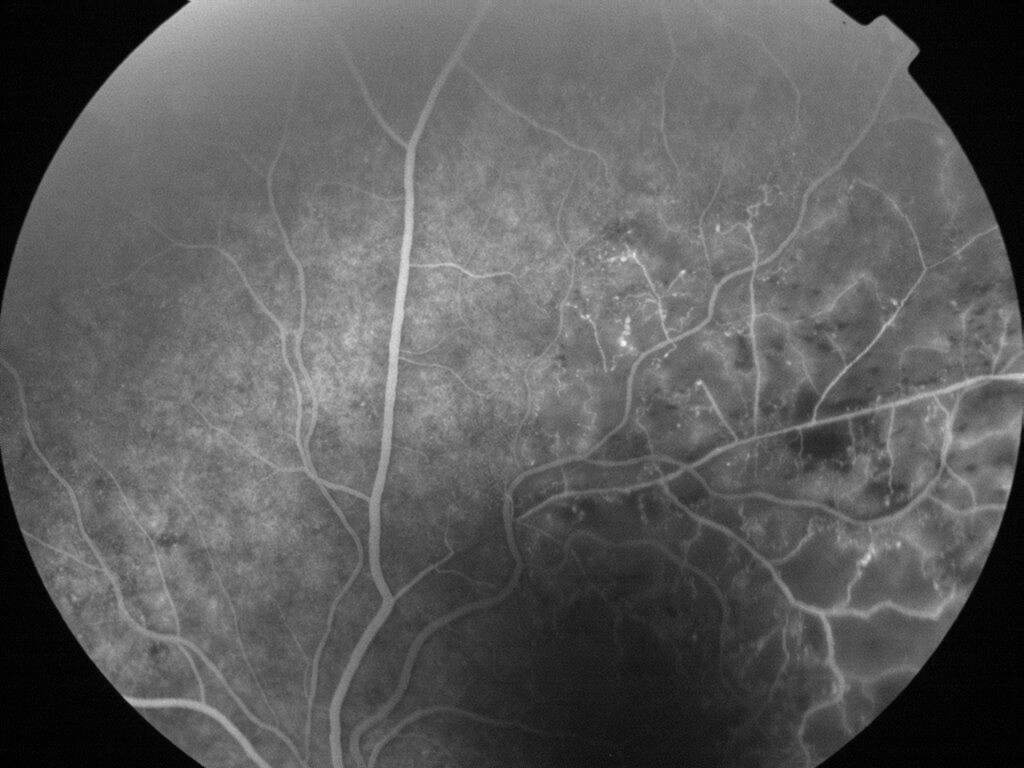

OCCLUSION DE BRANCHE DE LA VTS DE FORME ISCHEMIQUE MAJEURE